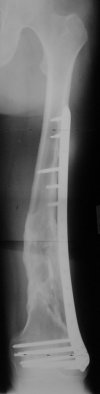

I presented a series of ~25 such cases at EuroTrauma'2004. Many cases were discussed here. I attach am example. Look also recent cases at http://www.hwbf.org/hwb/conf/alex58/scfx.htm,

At that moment we had in stock only the 10 mm solid nails so of course there was no idea about early weight bearing. But it was quite enough for early knee ROM excersises (see attached). Two locking screws through the distal block provided that.